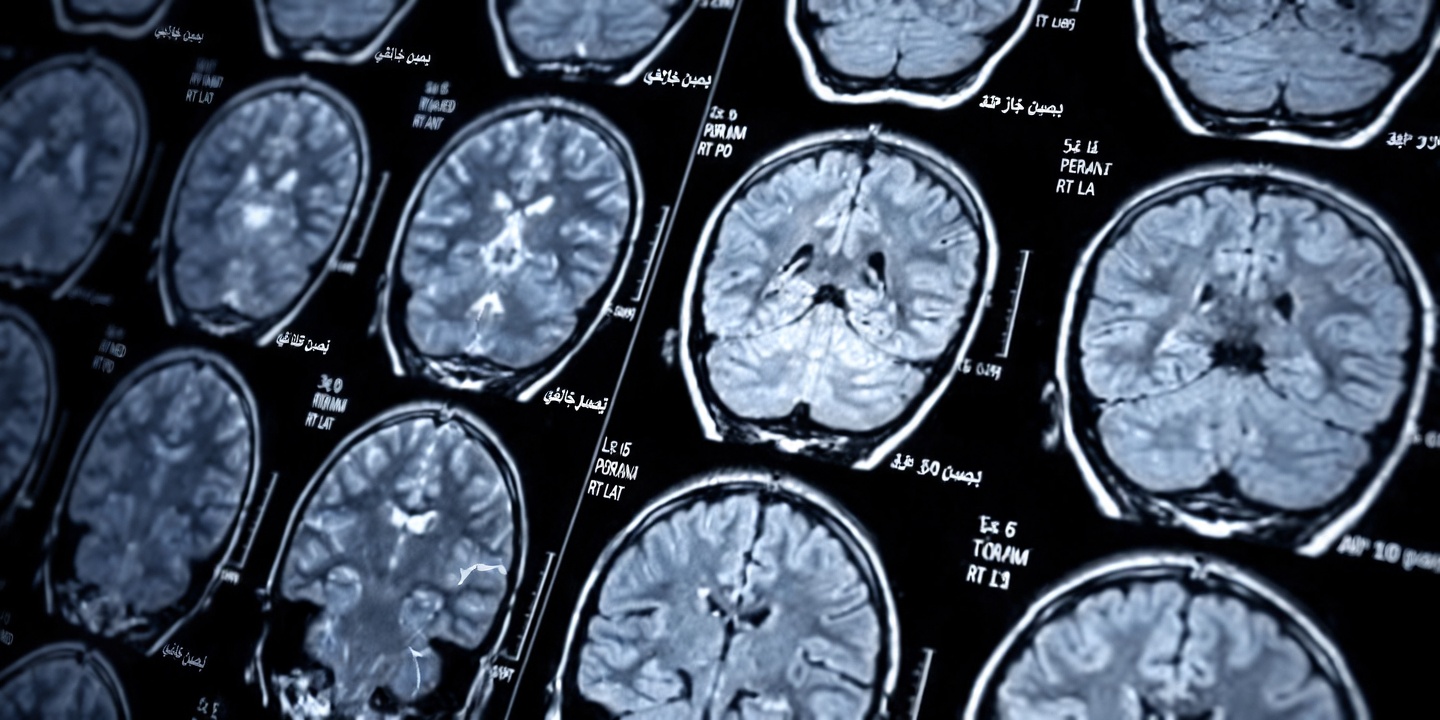

السكتة الدماغية الجوبية: خطر صامت بعد سن الستين

تحدث السكتات الدماغية الجوبية (Lacunar Stroke) غالبًا بهدوء لدى الأشخاص فوق 60 عامًا، فتترك أذيات صغيرة وعميقة في الدماغ دون أعراض درامية واضحة. قد تفسّر تعثّرًا بسيطًا أو لحظة ضباب ذهني على أنه “مجرد تقدّم في السن”، لكن علامات التحذير المبكرة قد تتراكم تدريجيًا لتؤثر في التوازن، والذاكرة، والقدرة على الاعتماد على النفس.

عند بلوغ الستين، تظهر تغيّرات كثيرة يُنسب معظمها تلقائيًا إلى الشيخوخة. لكن بعض هذه التغيّرات قد يكون ناتجًا عن انسداد شرايين دقيقة داخل الدماغ (مرض الأوعية الصغيرة)، ما يؤدي إلى سكتات صغيرة متكررة “تسرق” القدرة على الحركة والتفكير بوضوح على مراحل.

تكمن المشكلة في أن كل حدث قد يكون محدودًا، لكن تأثيره التراكمي قد يُحدث أذى في مناطق مثل المهاد (Thalamus) والعقد القاعدية (Basal Ganglia) والمادة البيضاء؛ ومع مرور السنوات قد يظهر ذلك على شكل فقدان تدريجي للاستقلالية. وتشير دراسات سكانية إلى أن حدوث هذه السكتات وعلاماتها يصبح أكثر شيوعًا بعد سن 60، لذا فإن فهمها يساعدك على مناقشة الأعراض بجدية مع الطبيب بدلًا من اختزال كل شيء في “عمر طبيعي”.